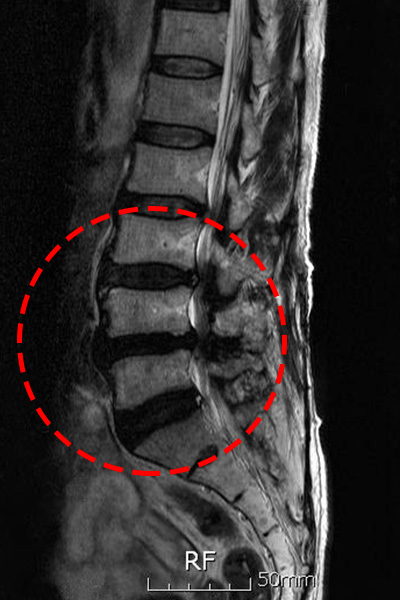

퇴행성 변화

가장 흔한 이유 중 하나는 퇴행성 변화입니다. 나이가 들어감에 따라, 척추의 디스크와 다른 구조물들이 시간이 지나면서 자연스러운 마모를 겪게 됩니다. 이로 인해 허리의 유연성과 지지력이 감소하게 되며, 척추관의 공간이 좁아지는 협착이 발생할 수 있습니다.

특히 중장년층에서 퇴행성 척추협착증이 빈번하게 발생하는 이유는 디스크의 수분 손실과 손상 때문입니다. 연세가 많은 분들은 특히 디스크의 수명이 줄어들고, 그로 인해 허리의 구조가 변형되며 신경이 압박을 받게 됩니다.